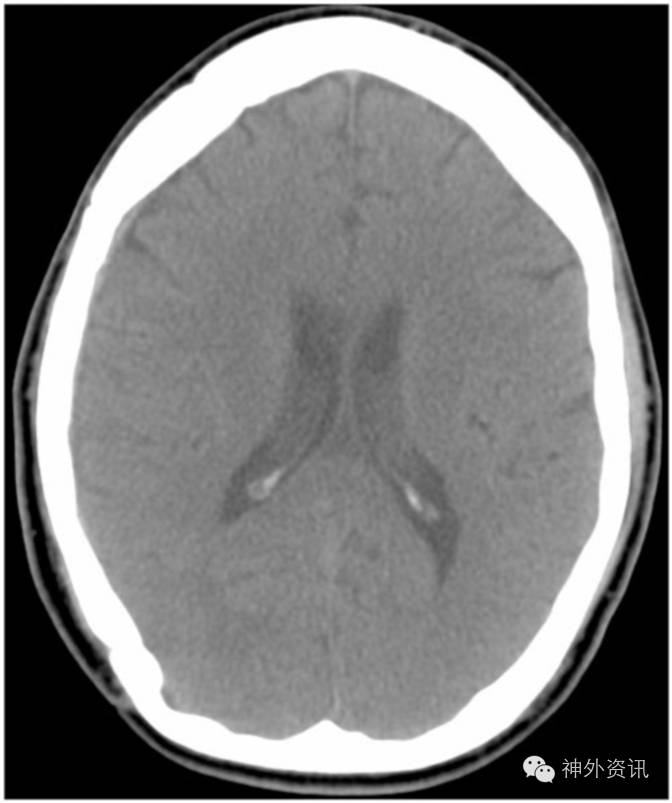

图2. 硬膜外血肿清除术后随访期间的CT扫描图像。